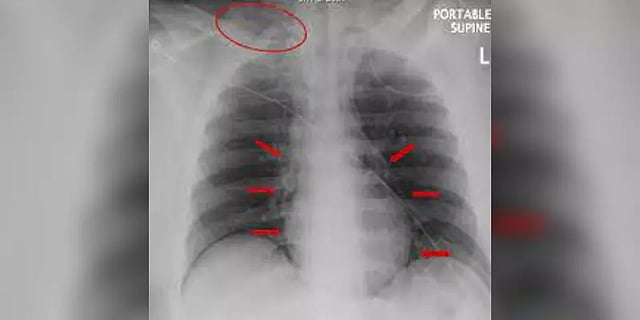

சுவிட்சர்லாந்தைச் சேர்ந்த 20 வயது இளைஞர் கடுமையான மார்பு வலியுடன் தீவிரச் சிகிச்சைப் பிரிவில் அனுமதிக்கப்பட்டார். நோயாளியின் முகம் வீங்கியிருப்பதை கவனித்த மருத்துவர்கள் அவர் சுவாசிக்கும்போது தனித்துவமான சத்தம் கேட்பதையும் கண்டறிந்தனர். மருத்துவர்கள் செய்த பரிசோதனையில் அவருக்கு தீவிர மூச்சுத்திணறல் ஏற்பட்டு நுரையீரலில் காற்றறைகள் கிழியும் அளவுக்கு பாதிப்பு ஏற்பட்டுள்ளது தெரியவந்தது. செயற்கை சுவாசத்தில் சிகிச்சை அளிக்கப்பட்டு இயல்பு நிலைக்கு திரும்பிய பின்னர், மேற்சிகிச்சைக்காக இளைஞரிடம் எவ்வாறு மூச்சுத்திணறல் ஏற்பட்டது என்பது குறித்து விசாரித்தனர். அப்போது அவர் கூறிய காரணம்தான் மருத்துவர்களை அதிர்ச்சியடைய வைத்துள்ளது.

20 வயதான அந்த இளைஞர் படுக்கையில் படுத்தபடி சுய இன்பம் செய்து கொண்டிருந்தபோது திடீரென மூச்சுத் திணறல் ஏற்பட்டு இந்த நிலைக்கு தள்ளப்பட்டதாக அவர் கூறியுள்ளார். அதன்பின்னர் தான் இளைஞருக்கு “நிமோமெடியாஸ்டினம்” எனப்படும் ஒரு அரிய நுரையீரல் பாதிப்பு ஏற்பட்டிருப்பதை உறுதி செய்தனர். நுரையீரல் அல்லது உணவுக்குழாயில் ஏற்படும் உடல் ரீதியான அதிர்ச்சியால் நிமோமெடியாஸ்டினம் (pneumomediastinum) ஏற்படலாம். மார்பு குழிக்குள் அழுத்தம் திடீரென அதிகரிப்பதால் நுரையீரலில் உள்ள காற்றுப் பைகள் சேதமடைந்து அதிக அளவு ஆக்ஸிஜன் தேவைப்படும் நிலை உருவாகும்.